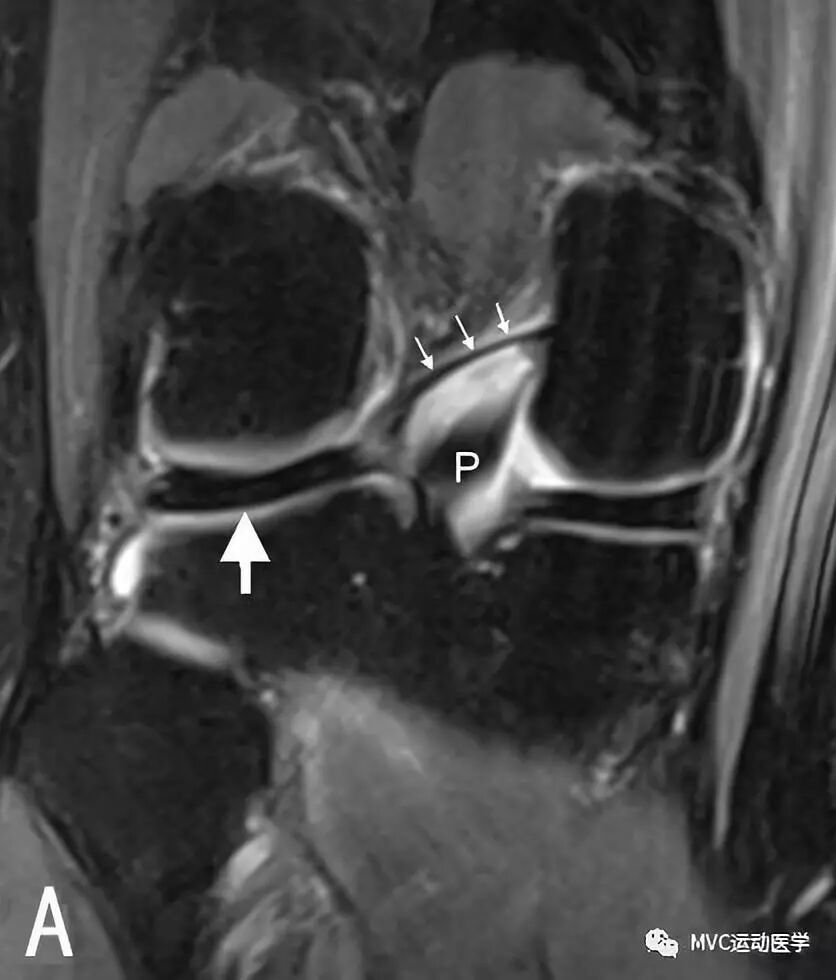

A:冠状位MRI显示外侧半月板后角(白色粗箭头)与Wrisberg韧带(白色细箭头),P代表后交叉韧带

B:矢状位MRI连续扫描,黑色箭头所指为Wrisberg韧带

半月板股骨韧带的半月板附着处易与外侧半月板后角的撕裂相混淆。韧带与半月板之间有液体或脂肪填充,可在MRI表现为由前上至后下的斜行撕裂。当膝关节外旋时,半月板股骨韧带与半月板之间的间隙更加明显,Wrisberg束比Humphrey束更易被误认为是半月板撕裂。